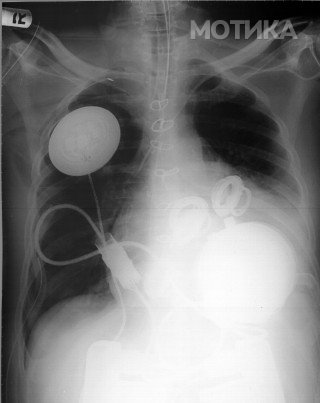

5. Вештачко срце AbioCor